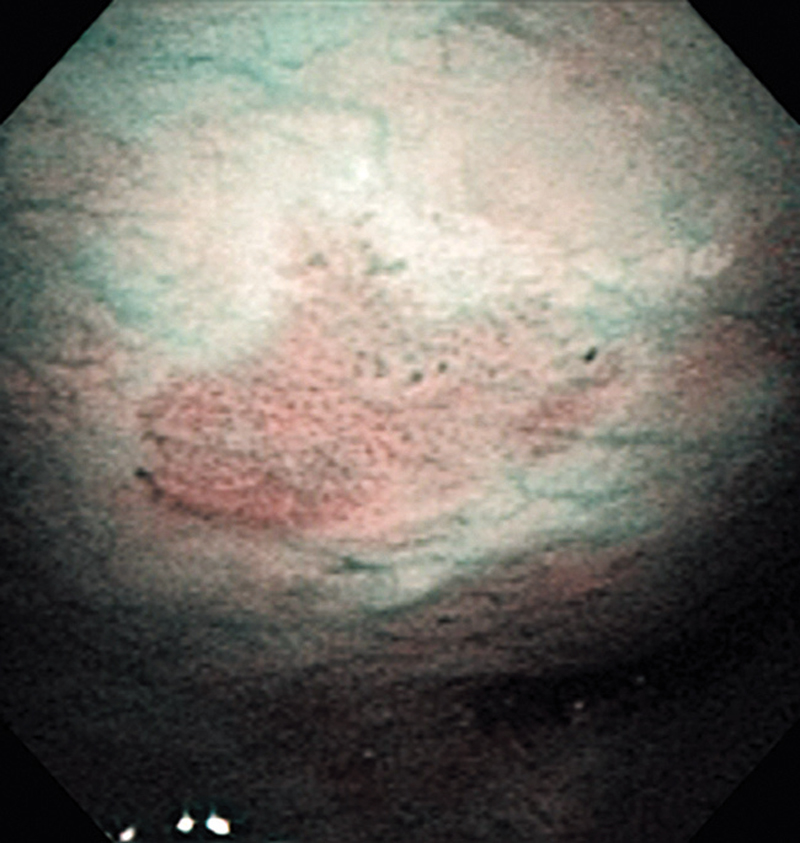

The lesion was detected on the oropharyngeal posterior wall in a periodic laryngopharyngoscopic NBI examination after an esophageal carcinoma surgery.

The NBI image showed a brownish, slightly-elevated lesion. In the conventional white light image, the same area was recognized as a slightly-whitish elevated lesion.

The lesion was treated with endoscopic mucosal resection and diagnosed as a squamous cell carcinoma in situ.